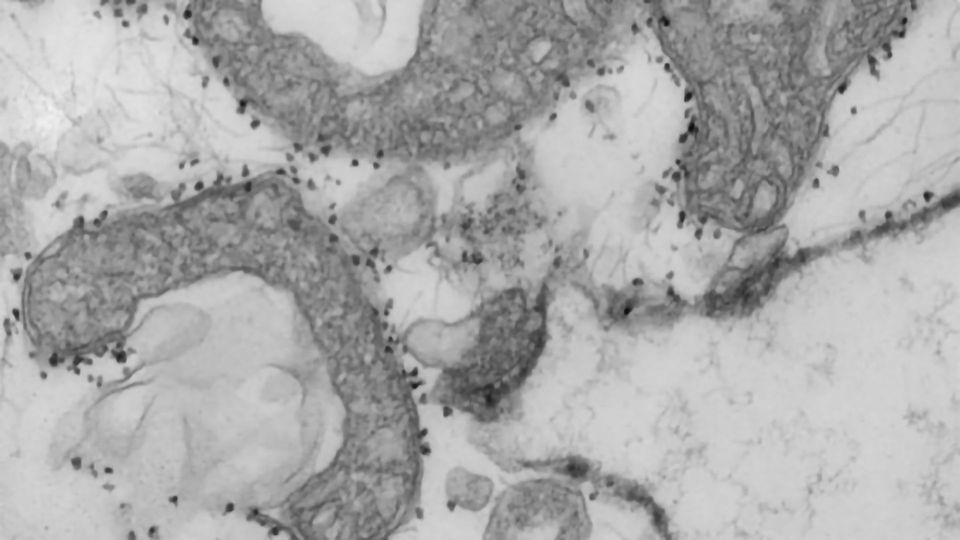

Pictured are damaged mitochondria (dark grey areas) released from human lungs. The small dark dots surrounding the mitochondria are magnetic beads that carry antibodies used to isolate and study unhealthy mitochondria that have been released from dying tissues. Credit: Wandy Beatty

The blood test measures levels of mitochondrial DNA, a unique type of DNA molecule that normally resides inside the energy factories of cells. Mitochondrial DNA spilling out of cells and into the bloodstream is a sign that a particular type of violent cell death is taking place in the body.

"Viruses can cause a type of tissue damage called necrosis that is a violent, inflammatory response to the infection," Gelman said. "The cell breaks open, releasing the contents, including mitochondrial DNA, which itself drives inflammation. In COVID-19 patients, there has been anecdotal evidence of this type of cell and tissue damage in the lung, heart and kidney. We think it's possible that measures of mitochondrial DNA in the blood may be an early sign of this type of cell death in vital organs."